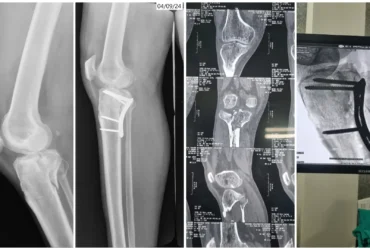

Right PCL Avulsion Fracture Treated with PCL Avulsion Fixation | Balanku Hospital

Huligeppa with right PCL avulsion fracture and knee instability underwent successful PCL avulsion fixation at Balanku Hospital and achieved complete recovery of knee range of...

We Provide Orthopedic Service by Experience Doctors

We has a dedicated multidisciplinary team that cares for and surgically repairs acute fractures for patients of all ages. We offer expertise in fractures of the hip, arm, leg, hand, foot and ankle.